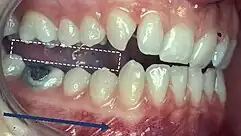

Incisor and molar classification

Classification of occlusion and malocclusion plays an important role in diagnosis and treatment planning in orthodontics. In order to describe the relationship of the maxillary molars to the mandibular molars, the Angle’s classification of malocclusion has commonly been used for many years.[8] This system has also been adapted in an attempt to classify the relationship between the incisors of the two arches.[9]

Molar Relationship

When discussing the occlusion of the posterior teeth, the classification refers to the first molars and may be divided into three categories:

- Class I: The mandibular first molar occludes mesially to the maxillary first molar, with the mesiobuccal cusp of maxillary first molar occluding in the buccal groove of mandibular first molar

- Class II: The mesiobuccal cusp of the maxillary first molar occludes anterior to the buccal groove of the mandibular first molar

- Class III: If the mesiobuccal cusp of the maxillary first molar occludes posterior to the buccal groove of the mandibular first molar[8]

Any deviation from the normal relation of teeth (Class I) is considered a malocclusion.

Class I relationships are thought to be “ideal”, however this classification does not take into consideration the positions of the two TMJ’s . Class II and III molar and incisor relationships are thought to be forms of malocclusion, however not all of these are severe enough to require orthodontic treatment. The Index of Orthodontic Treatment Need is a system that attempts to rank malocclusions in terms of significance of various occlusal traits and perceived aesthetic impairment.[11] The index identifies those who would benefit most from orthodontic treatment and onward referral to an orthodontist.